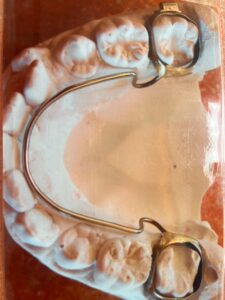

- Festsitzende und herausnehmbare Spangen: Wir bieten verschiedene Optionen von festsitzenden und herausnehmbaren Spangen an, um Ihren individuellen Bedürfnissen gerecht zu werden.

Zur Veranschaulichung unserer Arbeit zeigen wir Ihnen gerne Vorher- / Nachherbilder von kieferorthopädischen Behandlungen, um Ihnen einen Einblick in mögliche Ergebnisse zu geben.